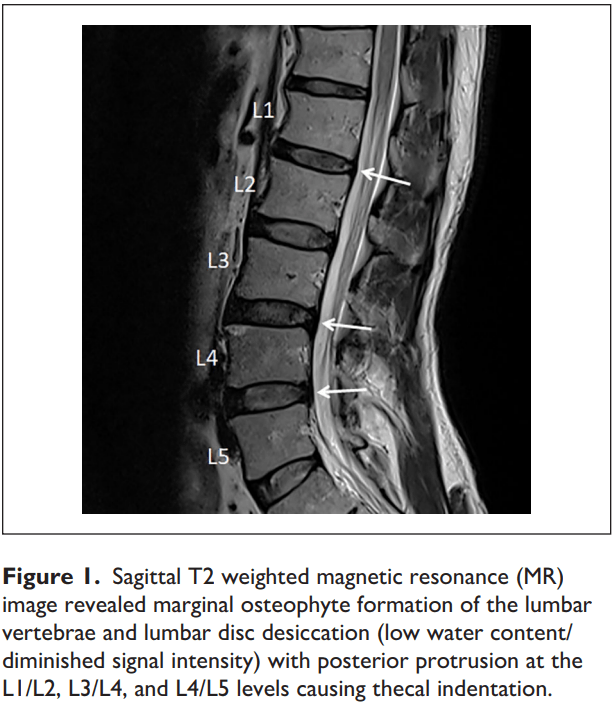

in MRIConfirmed Lumbar Disc Herniation Patients Treated with Spinal Manipulation Disc Herniation Disc herniation can be categorized as protrusion (disc contained by the annulus fibrosus), extrusion (disc materials migrated. Relevant case reports, review articles, surveys, and investigations regarding treatment of lumbar disk herniations with spinal manipulation and. The author's conclusion appears to be that there is some suggestion of an early benefit of spinal manipulation in patients with. Symptomatic, mri confirmed, lumbar. Spinal Manipulation Disc Herniation.